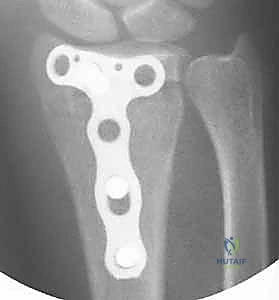

4. وضع الشريحة والتثبيت بالمسامير

بمجرد أن يصبح العظم في موضعه الصحيح، يتم وضع الش